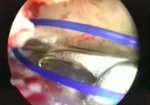

Arthroscopically assisted AC joint stabilisation with Tripod Technique

Surgical stabilisation of the AC joint through a combined arthroscopic and mini-open technique.

read more ↘ first part the classical fixation from the lateral clavicle to the coracoïd and the acromion is demonstrated, followed by a newer Tripod technique with fixation from the lateral clavicle to the coracoïd, acromion and scapular spine.